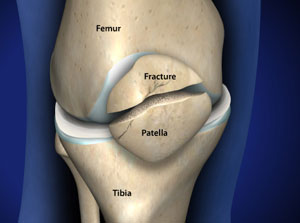

Fracture after Knee Replacement Surgery Complete Orthopedics store, Peri prosthetic trans patellar fractures after Total knee store, Post op Knee Pain Common causes store, Peri prosthetic trans patellar fractures after Total knee store, Patella Fracture Baton Rouge Kneecap Fracture Knee Joint Pain store, Patellar Fractures Broken Kneecap OrthoInfo AAOS store, Patellar Fractures Broken Kneecap OrthoInfo AAOS store, Treating Patella Fracture Broken Knee Cap in Plano Frisco store, Patella Fracture Orthopaedic Trauma Association OTA store, Patellar Fractures Broken Kneecap OrthoInfo AAOS store, Patella Fracture treatment Patella Fracture surgery store, Clunking Knee after Knee Replacement Complete Orthopedics store, Kneecap Fractures Patella Fractures Johns Hopkins Medicine store, Knee Replacement Surgery Details Recovery store, My knee still hurts after knee replacement surgery is this normal store, Pain after Knee Replacement Complete Orthopedics Multiple NY store, Patellar Fractures Broken Kneecap OrthoInfo AAOS store, Patellar Fracture Fractured Knee Cap PhysioAdvisor store, Patellar Kneecap Fracture Boston Medical Center store, Patella Fracture Orthopaedic Trauma Association OTA store, Patella Fracture Broken Knee Cap orthopedic specialist prescott store, Swelling after Total Knee Replacement Complete Orthopedics store, What is a Partial Knee Replacement store, Knee Replacement Complications Problems After Knee Surgery store, Patellar Kneecap Fracture Boston Medical Center store, Patella Fracture or a Broken Kneecap store, Patellar Fractures Broken Kneecap OrthoInfo AAOS store, Patella Fracture Broken Knee Cap Orthoriverside store, Benefits of Chiropractic Therapy After a Knee Replacement store, Complex Total Knee Replacement Boston MA Knee Fracture Worcester MA store, After Surgical Kneecap Alignment Patient Education UCSF Health store, Patella Fracture Repair store, Knee Replacement Surgery Risks and What to Expect store, Patella Fracture Orthopaedic Trauma Association OTA store, KNEE REPLACEMENT SURGERY AND SSD BENEFITS store.